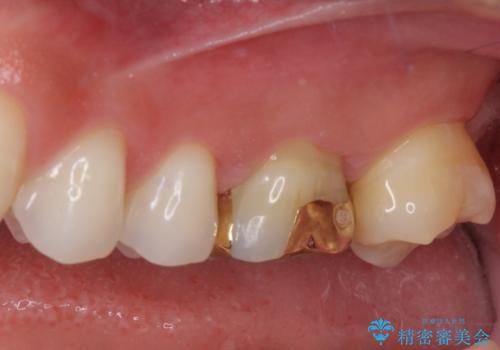

- 奥歯の詰め物が外れてしまったとのことで来院された患者様です。

幾度も詰め物治療を行ったため継ぎ接ぎだらけとなっていたため、インレーにて修復治療をすることとしました。

咬合力が強いため、ゴールド合金(PGA)のインレーを選択することとしました。